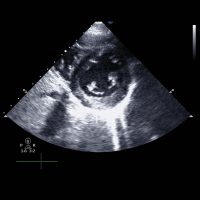

Echocardiogram (Echo)

An echo is an ultrasound scan of the heart. The test is used to acquire images of the heart, to identify if the heart is pumping effectively, if there’s a valve abnormality, or if there’s any previous damage to the heart.

Insurance: check with your provider

Procedure code: 5108

Stress Echo

This examination combines the imaging of transthoracic echo with a cardiac stress test. The stress is either physical exercise on a bicycle or treadmill or alternatively using a pharmacological agent to stress the heart. The test is used to assess the effects of your cardiac condition during stress and takes approximately 45 minutes. Please check with your insurance company to see if you are covered.

Procedure code: 5022